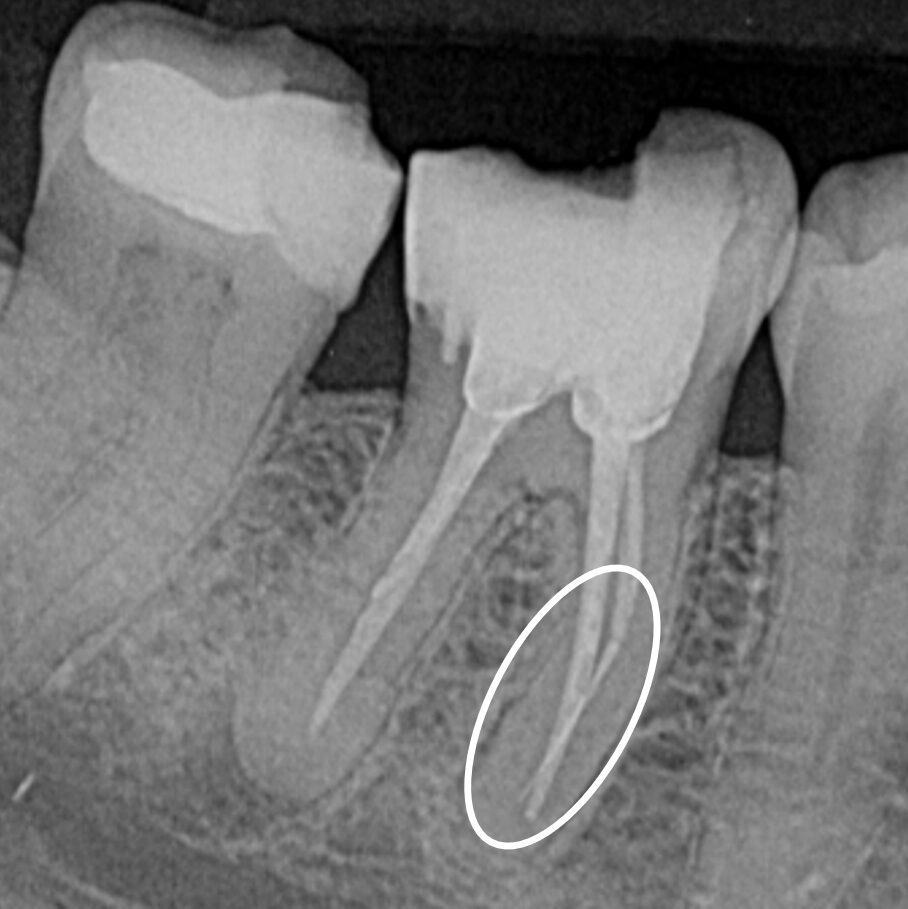

Dive into real-life cases where our products make the difference. From complex retreats to precision instrument retrieval, each case shows how innovation meets clinical success.